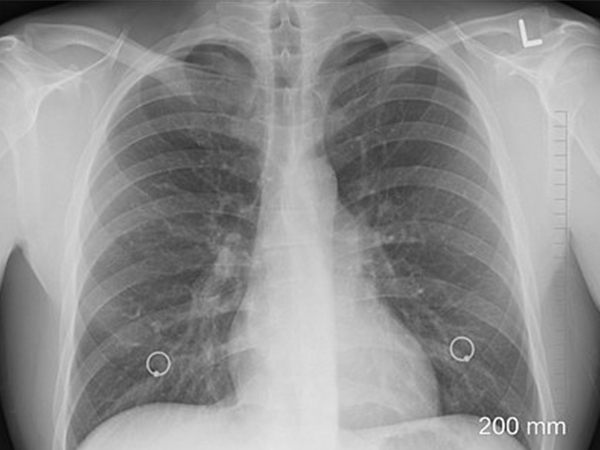

- Chest X-ray: This is used to check if the heart has enlarged due to excess fluid.